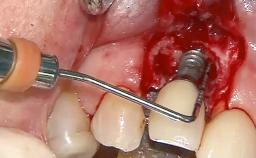

A 70-year-old female patient was referred by her general dentist to the periodontist for assessment and management of an infection associated with implant 36. The general dentist had noted suppuration on probing during examination.